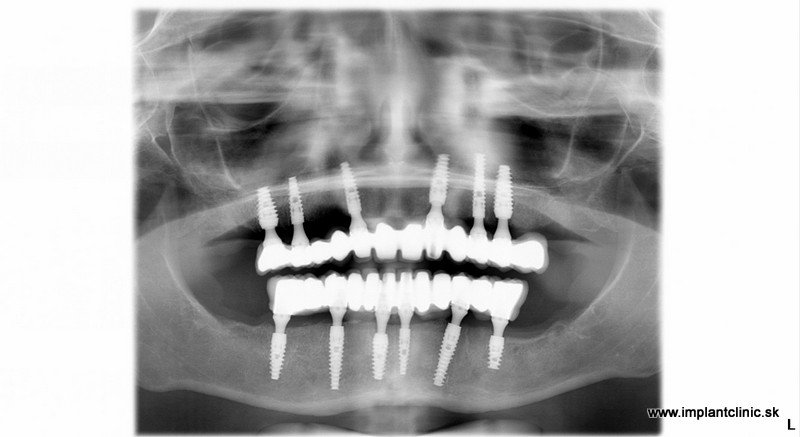

Finálny snímok po nasadení keramických mostíkov

Vrchná čeľusť : 5 extrakcií, 6 zubných implantátov, 12 – členný keramický mostík

Spodná čeľusť: 11 extrakcií 6 zubných implantátov 12 – členný keramický mostík

V prípade našej pacientky Jany sa po extrakciách začalo implantovať do oboch čeľustí. MUDr. Salka zaviedol spolu 12 zubných implantátov. Celé ošetrenie v tomto prípade trvalo 5 hodín. Je to maximálny počet hodín na ošetrenie v ambulantnej celkovej narkóze.

Potom nasleduje fáza hojenia, ktorá zvyčajne trvá 2-4 mesiace. Odobratie odtlačkov je predposledným krokom k vášmu novému úsmevu v Implantclinic. Výroba keramických mostíkov trvá našim zubným technikom približne 2 – 3 týždne. Keramické mostíky sa potom nasadia fixne na zahojené implantáty. Farbu zubných koruniek si pacient vyberá sám.